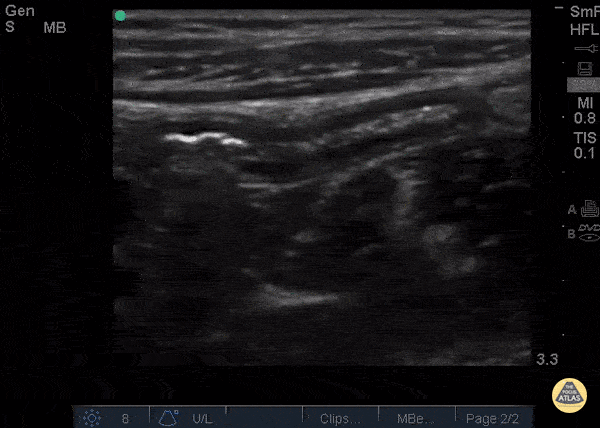

Bowel-GI - Normal Appendix blind end

12 y/o M with nausea vomiting fevers and vague “belly pain.” Patient mildly tender in suprapubic area. POCUS visualized a normal appendix is seen. A normal appendix is identified by a blind-ending tubular structure (as seen in this image). It should be <6mm diameter measured from outer wall to outer wall (although 6mm-7mm has also been described). This patient’s appendix was measure to be 5.1mm (see still image). Dr. Sathya Subramaniam - Children’s Hospital of Philadelphia